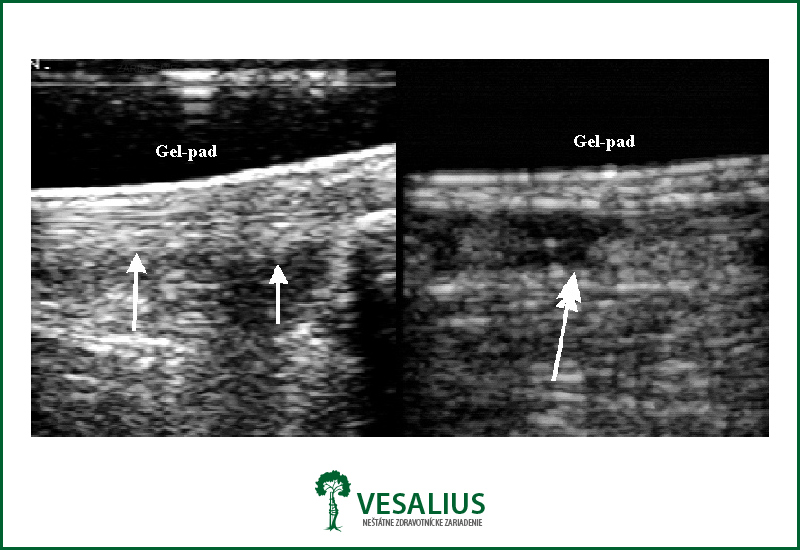

Diagnóza sa stanoví jednak vyšetrením, kedy v akútnom štádiu lekár hmatá jednoznačný defekt v oblasti ruptúry a tiež je oslabená sila pri pohybe v členku. Pri čiastočných ruptúrach je nápomocné vyšetrenie magnetickou rezonanciou resp. ulptrazvukom.